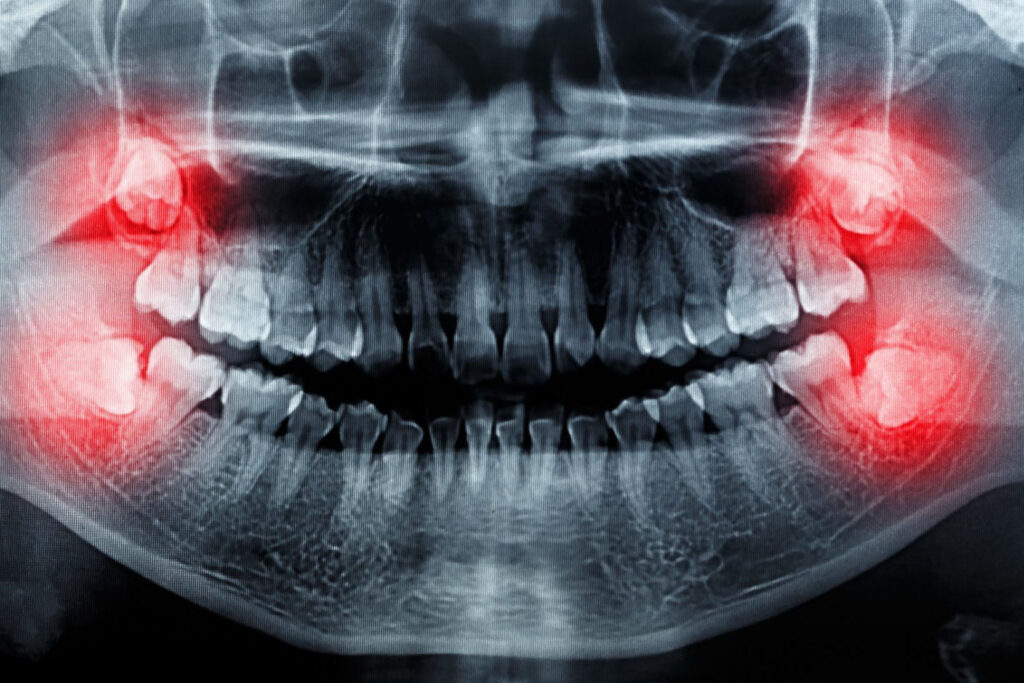

Die schlecht liegenden Weisheitszähne verursachen verschiedene Probleme, die man natürlich wahrnimmt. Wenn man keine Symptome hat, fragt man seinen Zahnarzt am besten nach seinem Zustand. Regelmäßige Röntgenaufnahmen können ihrem Zustand folgen, und so können sie mit den anderen Zähnen koordiniert werden.

Die Probleme kommen davon, dass unser Kiefer mit dem Fortschreiten der Evolution anatomisch kleiner geworden ist, infolgedessen haben diese Zähne keinen Platz mehr. Bei den meisten jungen Menschen – etwa bei drei von vier – gibt es anatomisch nicht genügend Platz für Weisheitszähne in der Reihe, so dass die Mehrheit der erwachsenen Bevölkerung früher oder später auf Schwierigkeiten stoßen wird.

Wenn sich herausstellt, dass die Weisheitszähne eine unregelmäßige Lage haben, aber keine Probleme verursachen, können sie für eine sehr lange Zeit unter regelmäßiger Kontrolle ungestört bleiben und müssen nicht entfernt werden.

Die Zahnentfernung wird empfohlen, wenn der Weisheitszahn so positioniert ist, dass keine Chance besteht, dass er durchbricht und wiederkehrende Entzündungen und Schmerzen verursacht. Wenn andere Beschwerden wie Karies oder wegen der schwierigen Reinigung Gingivitis auftreten, lohnt es sich auch, sie herauszuziehen.

Selten kommt es auch vor, dass auf der Grundlage einer Röntgenaufnahme Verdacht auf eine manchmal bösartige Veränderung besteht, in diesem Fall ist es natürlich auch wichtig, diese so schnell wie möglich zu entfernen.